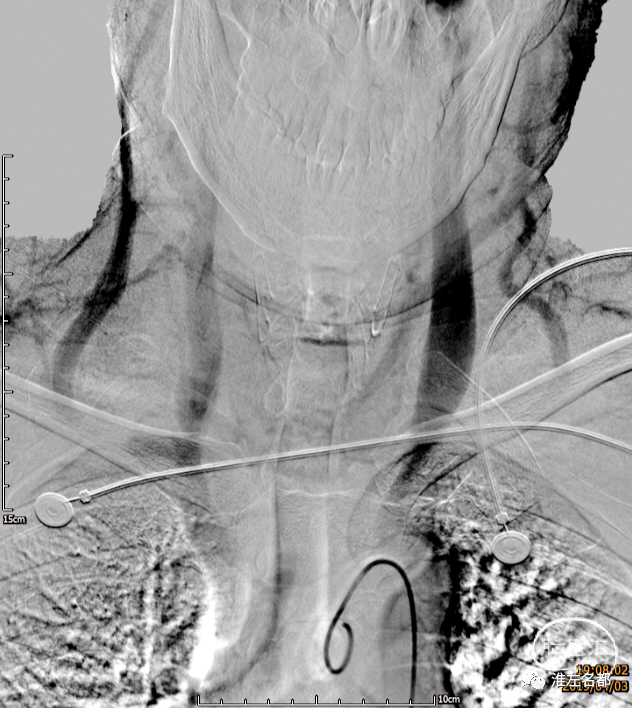

主动脉弓造影时,尽量扩大视野,造影需延迟到静脉晚期,上界包括横窦,下界到上腔静脉。这么做有两个目的,第一,了解颈部静脉的基本情况,为选择介入治疗通路提供必要信息;第二,部分脑静脉窦血栓患者会同时合并颈内静脉血栓(通常是单侧),一般多位于颈内静脉的远心段,也有累及整个颈内静脉的情况,少数情况下也可能合并头臂静脉血栓,主动脉弓大范围造影有助于显示颈内静脉血栓长节段闭塞,或头臂静脉内的大血栓,这些异常信息对制定合理介入治疗策略非常重要。

主动脉弓造影静脉晚期图像,

双侧颈内静脉、颈外静脉和上腔静脉显影通畅。

此为主动脉弓造影静脉晚期图像,

右侧左侧颈内静脉未见显影。